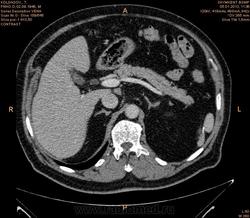

Помогите разобраться.Больной 2 мес назад обследован на узи бр.полости  чисто.(м.б. не опытный узист.)Беспокоять боль в правом подреберье, потеря веса нет.Анализы еще не готовы.

Гиподенсное образование в 8 сегменте, с накоплением по контуру в артериальную фазу, заполнением почти полностью в портальную, и опять гипо- в отсроченную. Пока думается на гемангиому, дифференцировать с гепатоцелюллярным раком, несмотря на отсутствие признаков цирроза. Сложновато  без дайкома.

Судя по времени, отсроченная через 7-8 мин от начала введения контраста (ФИО пациента убирайте, пожалуйста!). На мета, на мой взгляд, не похоже. Подождём, что еще коллеги скажут.

Вымывание контраста к венозной и равновесной фазам если не путаю более характрено для HCC.

имеет значение количество и скорость введения контраста

без диком создается впечатление что контраста либо мало было либо низкая скорость